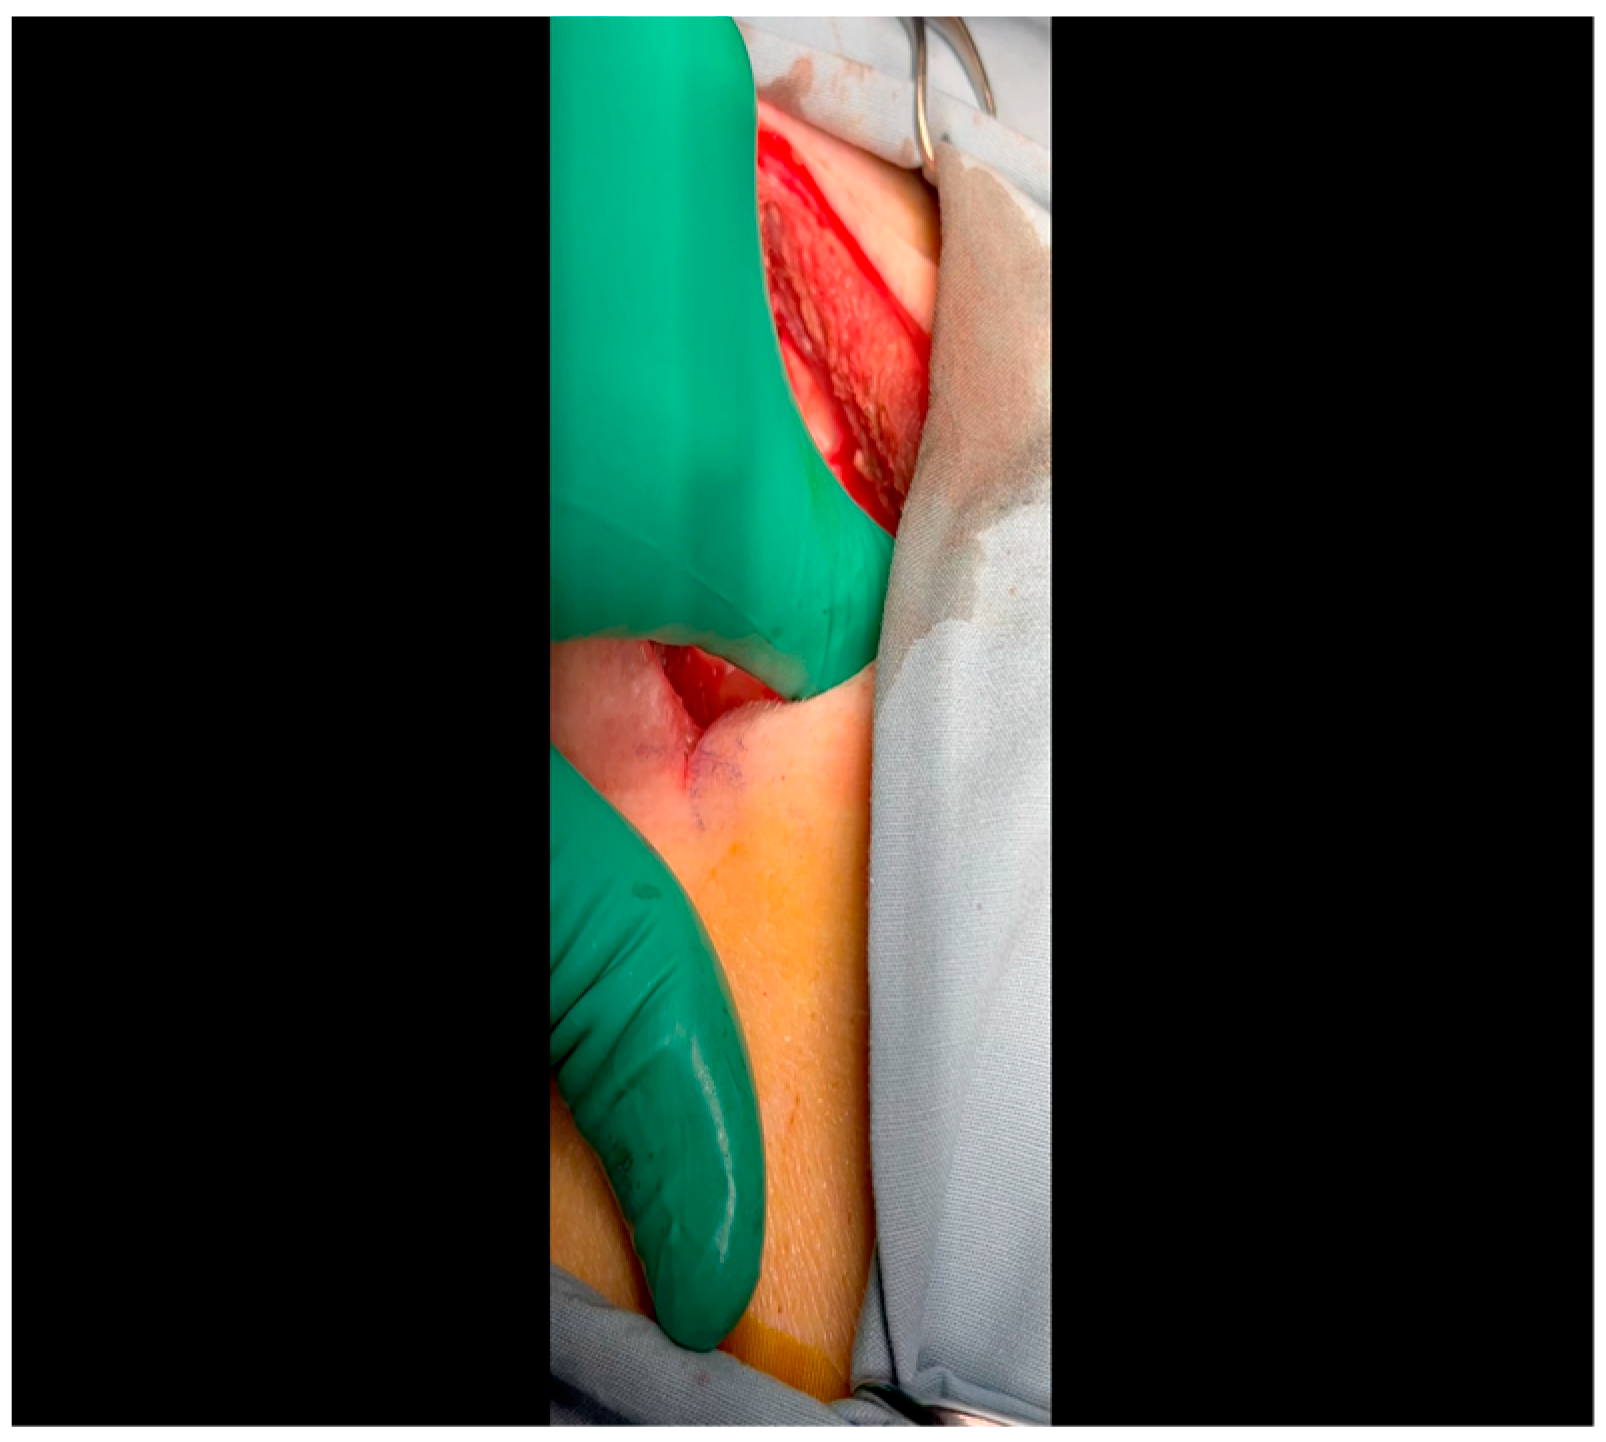

- A mini left thoracotomy is then performed: a transverse incision is made along the ribs beginning at the left sternal border and extending laterally for approximately 6 cm. This incision is placed just inferiorly to the left axillary fold (Figure 1).